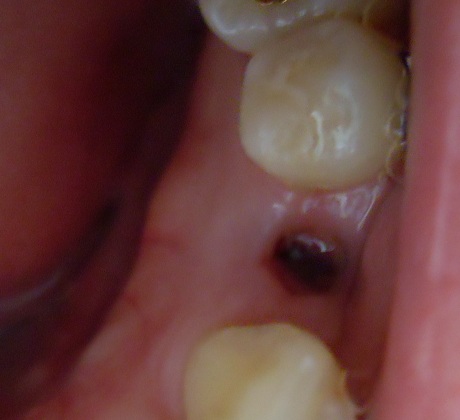

오른쪽 발치할 때

오라픽스 포스팅 사진 (5).JPG

(이 빼고 2일 된 사진)

발치보다 중요한건 관리겠죠? 발치 한 곳에 사진처럼 구멍이 생기는데 거기에 자꾸 음식물이

끼어요ㅠㅠ 그때 절대 이쑤시개나 치간 칫솔로 쑤시면 안된대요

꼭 물로 헹구어야 한답니다~